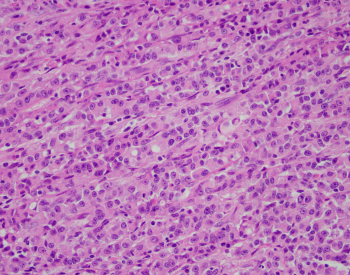

40 year old male found unresponsive. No medical or social history. The scene was unremarkable. External examination revealed scars on the forearms and legs. Autopsy revealed 450 g heart, edematous lungs, and firm liver.